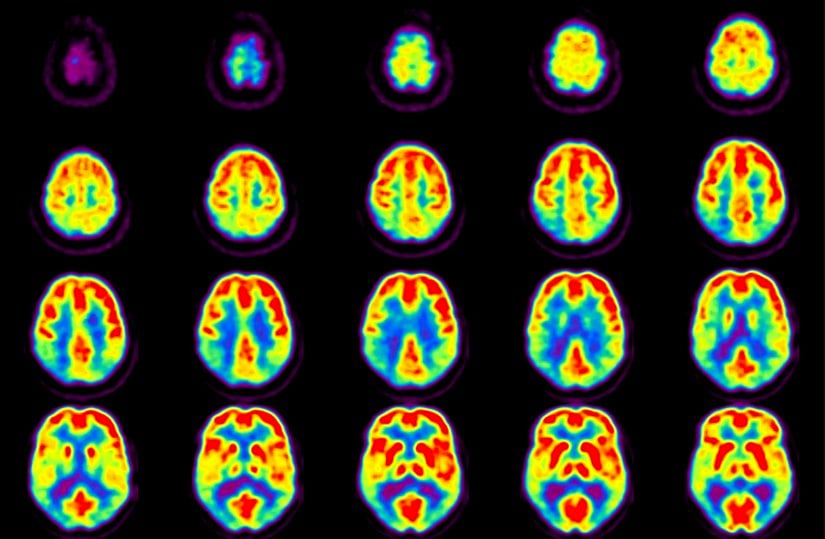

Beyin ve Merkezi Sinir Sistemi Hastalıkları

Glikoz, beynin en temel yakıtıdır. PET taramaları için hazırlanan ilaçlardaki izleyiciler, glikoz ve benzeri bileşiklere tutturulur. Bu şekilde tarayıcı, radyoaktif glikozu görüntüleyerek beynin en fazla oranda glikoz kullandığı bölgeleri tespit eder.

PET taramasının teşhis ve tedavisinde kullanıldığı bazı merkezi sinir sistemi hastalıkları şunlardır:

- Beyin tümörleri

- Alzheimer hastalığı

- Epilepsi

- Parkinson hastalığı

- Depresyon

- Kafa travması